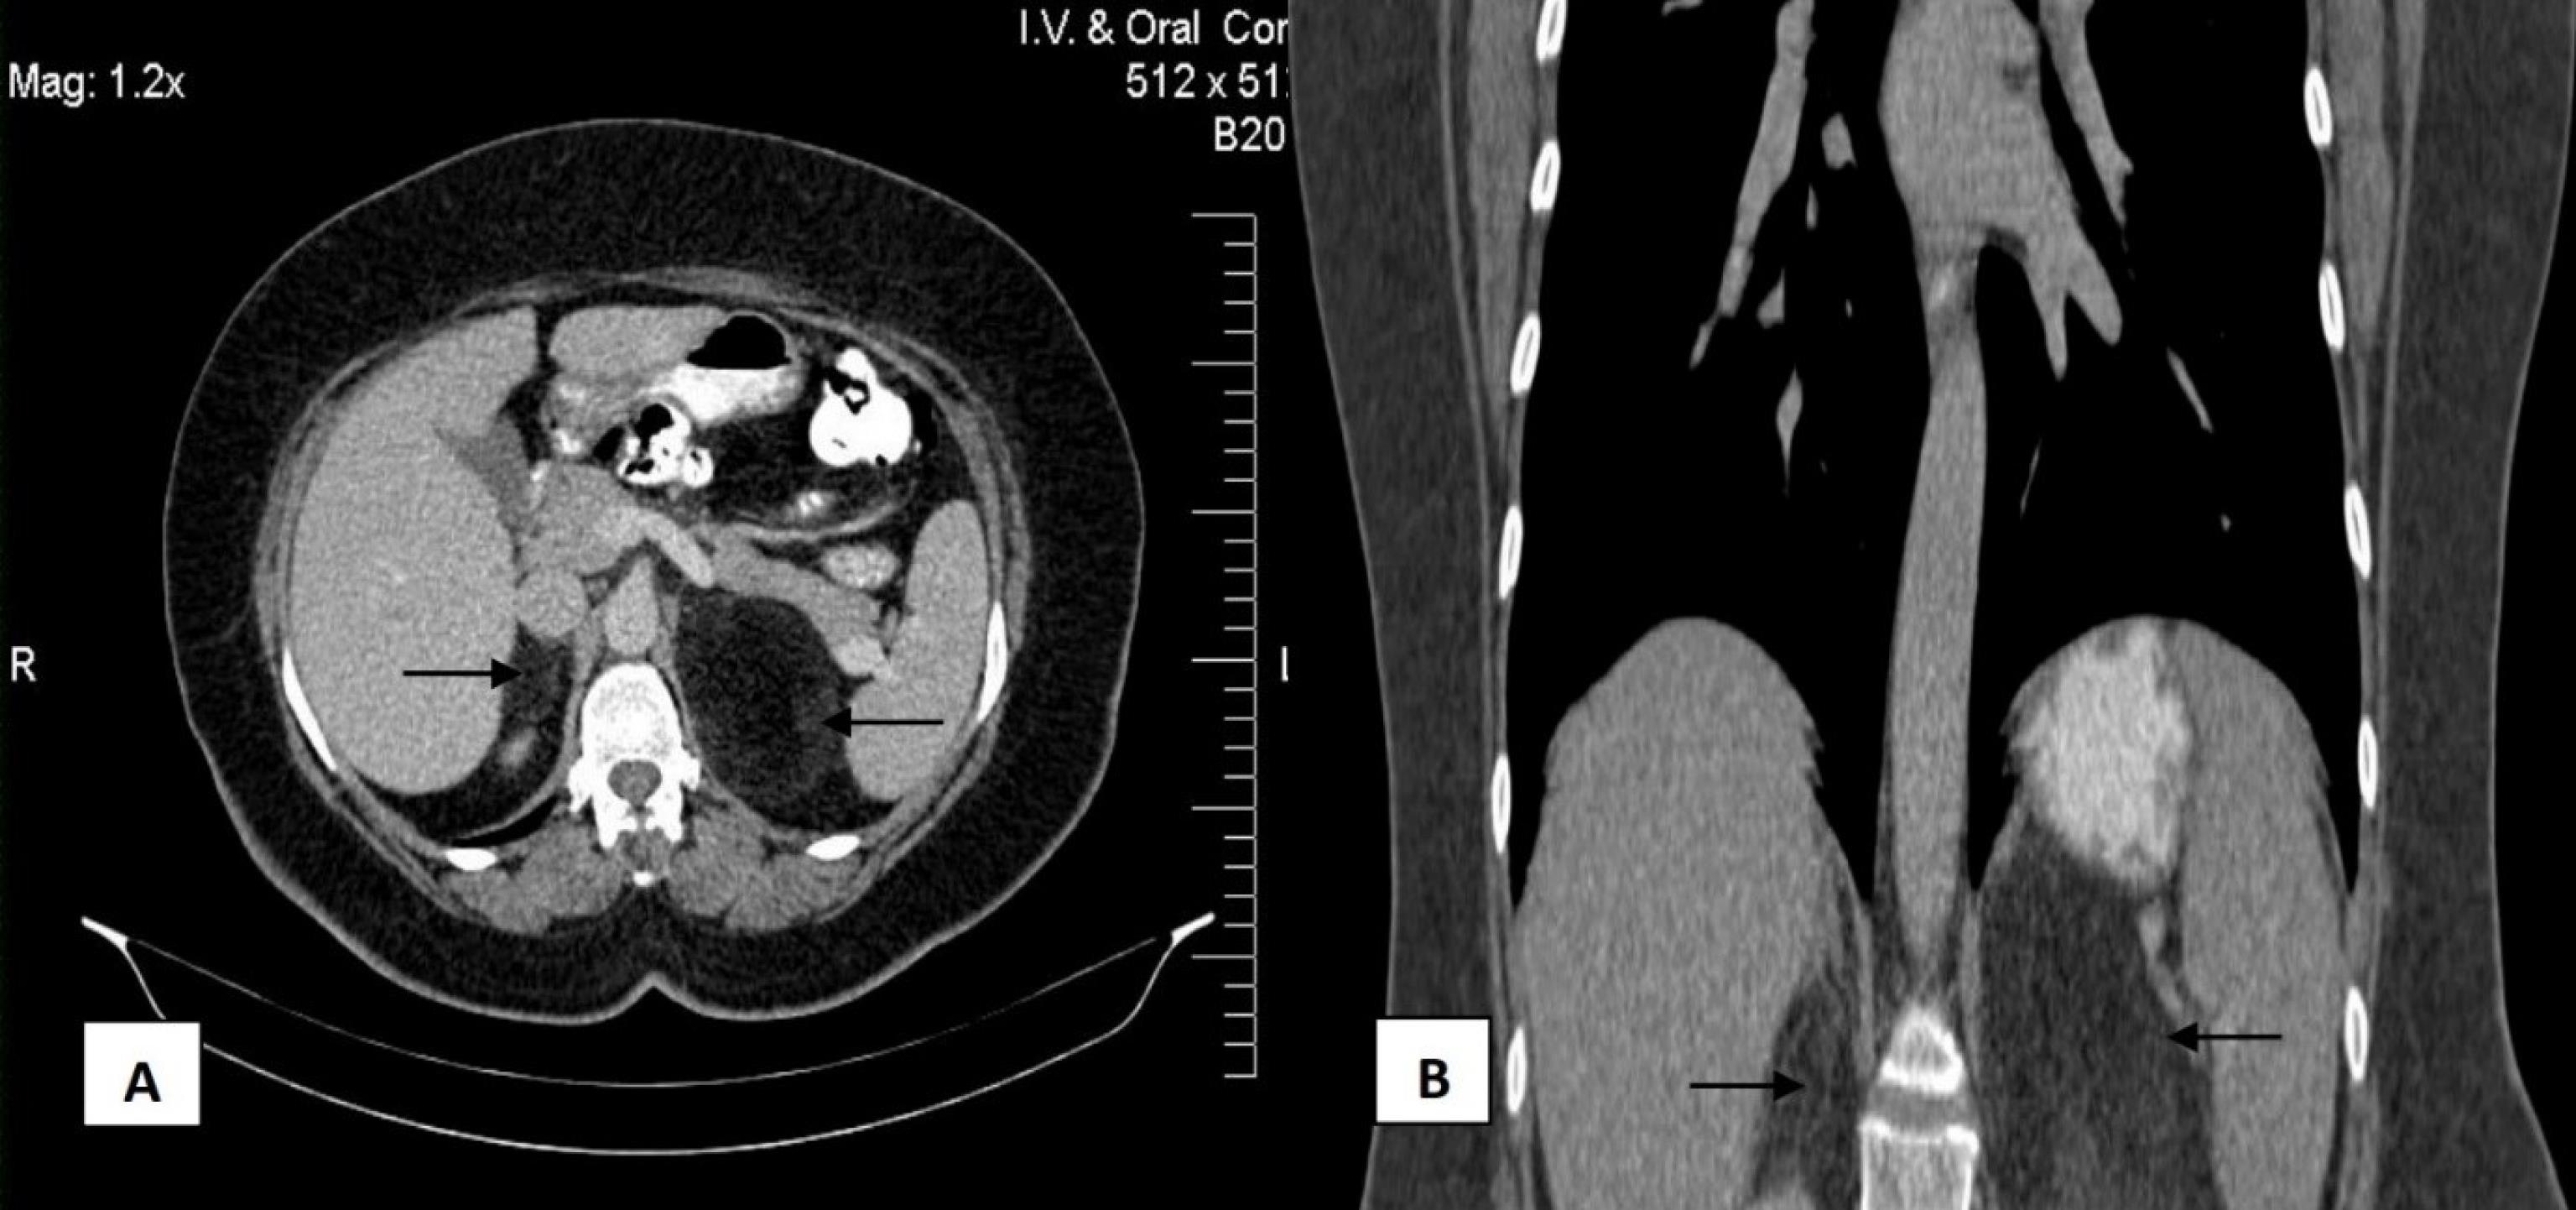

A 51-year-old female was referred to our clinic with a complaint of pain or discomfort in the abdomen that persisted for two months. The patient had no history of previous surgeries or known medical conditions. An evaluation of her vital signs, including blood pressure and heart rate, showed no significant alterations. Physical examination and cardiovascular assessments were also normal. Ultrasound examinations demonstrated a well-defined hyperechoic lesion measuring 62 × 68 mm adjacent to the upper pole of the left kidney and a similar lesion of 42 × 32 mm adjacent to the upper pole of the right kidney, indicating adrenal fatty masses. Chest x-ray showed no detectable abnormalities. The laboratory results of the patient’s blood count, biochemistry profile, and urine biochemistry markers were in the reference range. Moreover, evaluations of thyroid function showed no apparent abnormalities (Table 1). Complementary imaging assessment of the abdomen was performed using an intravenous contrast-enhanced computed tomography (CT) scan. The CT detected a well-defined 77 × 63 mm hyperdense lesion showing low attenuation [-71 Hounsfield unit (HU)], containing adipose and vascular tissue without calcification. In addition, a 55 × 40 mm fat-containing solid lesion with a thin capsule and no enhancement on the right adrenal gland was detected (Figure 1).

CT scan. (A) The cross-sectional CT scan shows bilateral lesions of the surrounded left and right renal with 77 × 63 mm and 55 × 40 mm, respectively. (B) The coronal-sectional CT scan